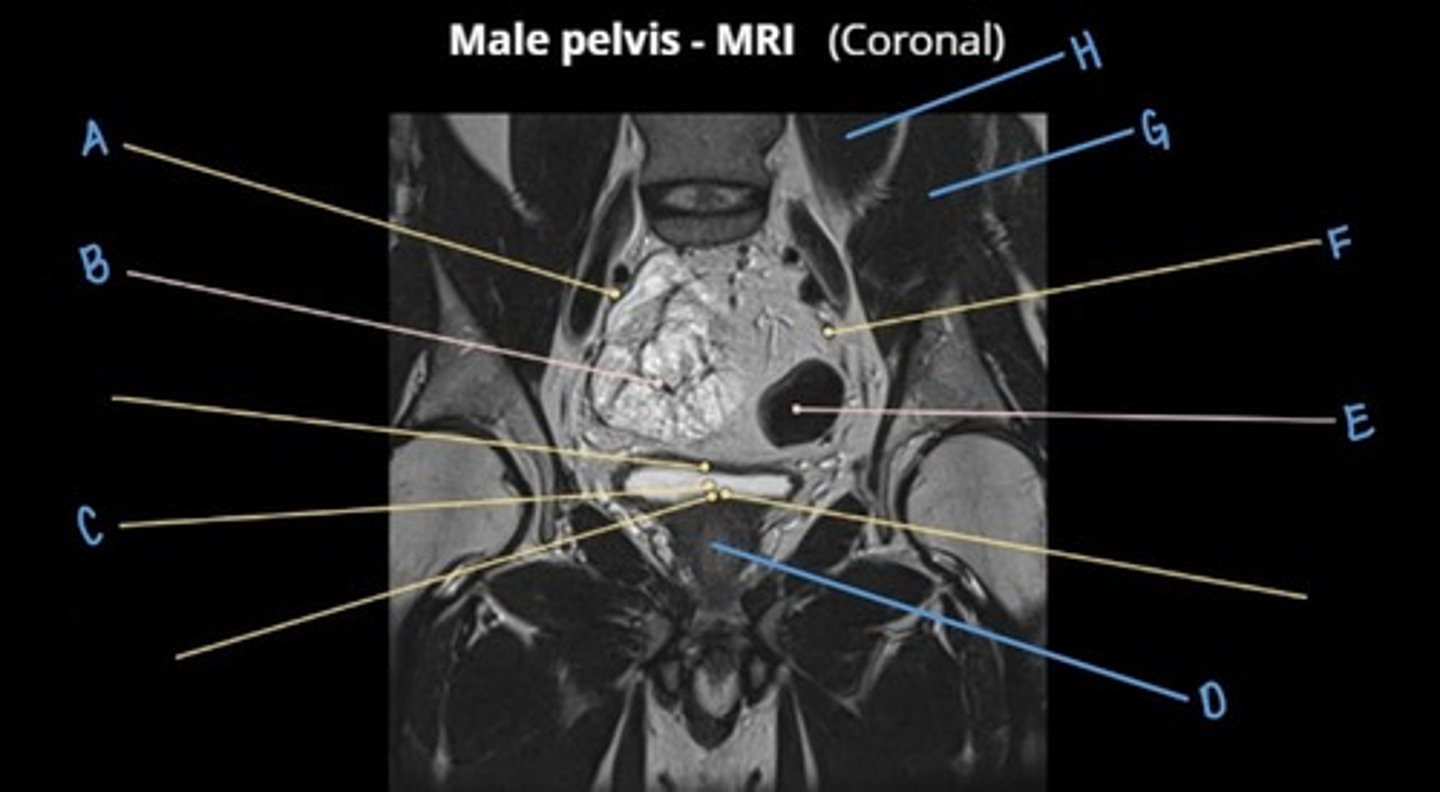

sigmoid colon

A

seminal vesicles

B

prostate

C

rectum

D

pubic symphysis

E

retro-pubic space

F

bladder

G